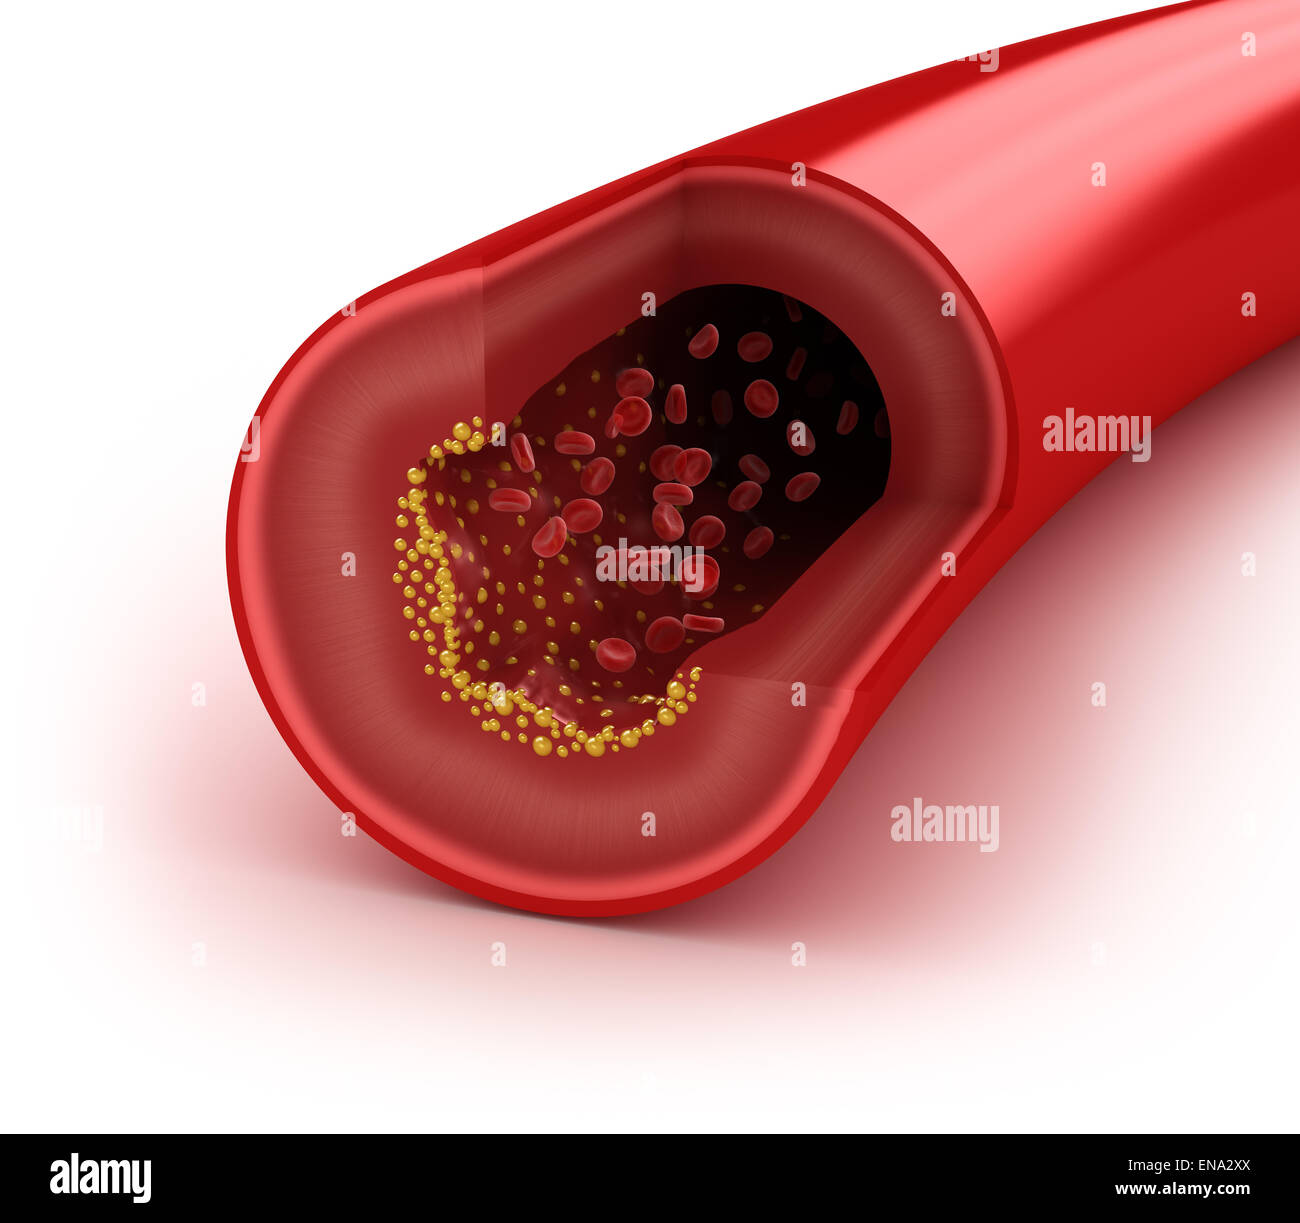

a deposit of plaque within the arterial wall

Cholesterol plaque in artery – Vida Abuelo

A typical blood vessel. ( a ) shows a normal artery with normal blood …

Artery Blockage caused by Plaque – TrialExhibits Inc.

Arterial plaque | Serrapeptase

Blood Clot, Plaque In Artery Restricting Blood Flow Stock Photo …